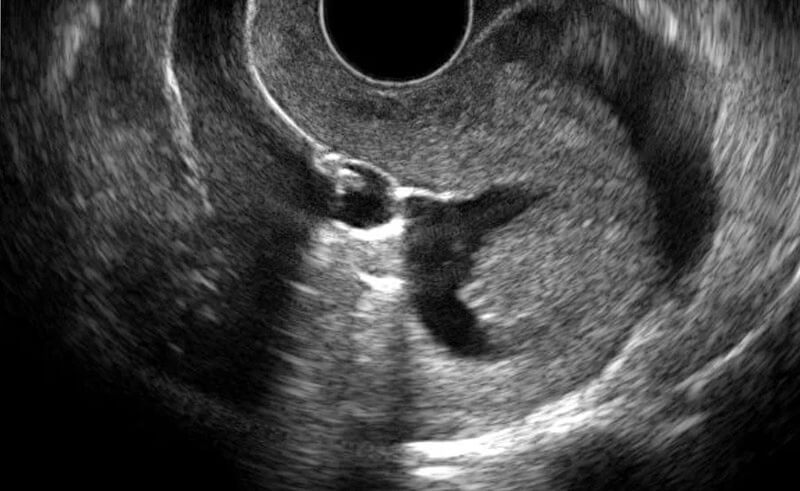

The sonohystogram procedure at Littleton Gynecology and Wellness is done in three parts: a transvaginal ultrasound, fluid insertion, and a final ultrasound. The transvaginal ultrasound gets imaging of the uterus pre-fluid and also allows our examiners to judge the pelvis. Afterward, our provider will use a speculum to keep the vagina open while they clean the cervix and insert a tube to flow fluid into the uterus; fluid makes the endometrium easier to see, which helps us identify bloodstream clots and other possible abnormalities.